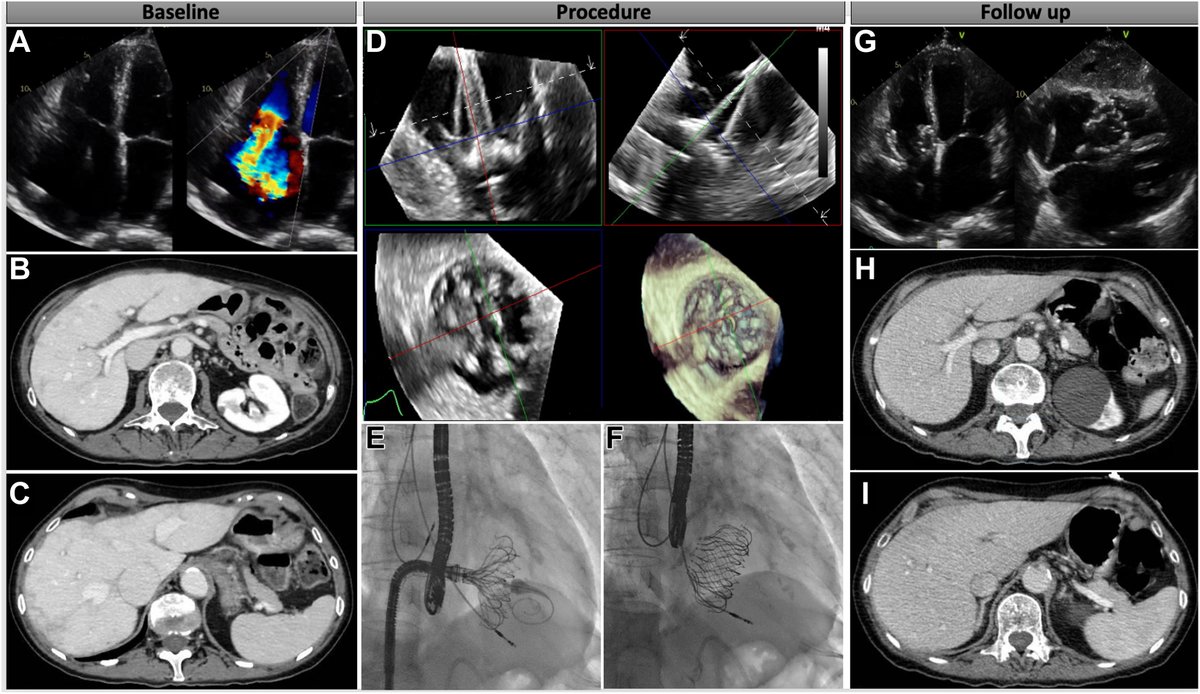

FANTASTIC MUST-READ #JACCIMG @JACCJournals SOTA review on Post #Evoque #TTVR Echo #TTE imaging. Comprehensive, practical! Download full paper here FREE for a LIMITED TIME! https://t.co/lfhJ0khJAw https://t.co/DgyCXnMOOF